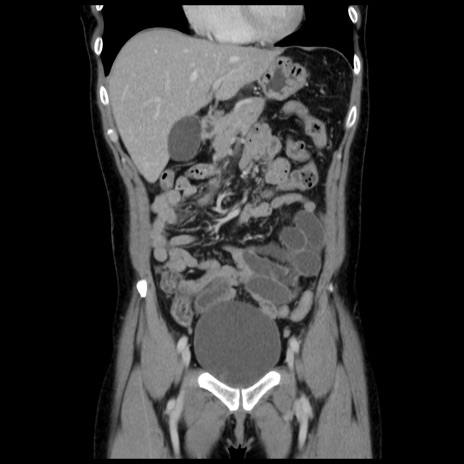

症例10(冠状断像)

【症例】 50歳代女性

【主訴】 腹痛

【現病歴】前日生レバーを食べた。今朝に排便あり。 昼前に突然発症の腹痛を生じ、当院救急外来を受診した。

【既往歴】 子宮筋腫にてで子宮全摘後

【身体所見】 意識清明、腹部:平坦、軟、下腹部やや左を中心に圧痛・反跳痛あり、筋性防御あり

【データ】WBC 7800、CRP 0.07